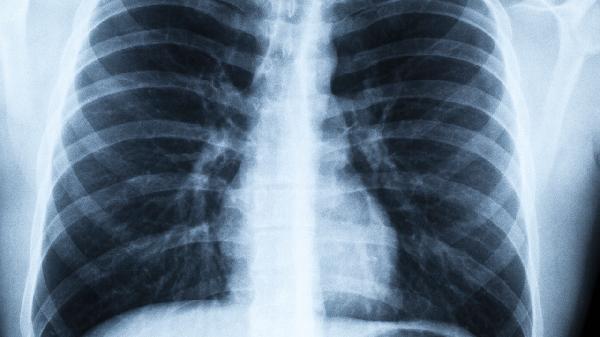

肺病都是“忍”出来的?医生:这几种症状,说明肺“病”得不轻了

肺病确实常常因为被忽视而延误治疗,但并非所有症状都意味着严重问题。关键在于学会识别那些真正需要警惕的信号。今天就来聊聊那些容易被“忍”过去的肺部求.救信号。

一、这些症状可能是肺在“求.救”